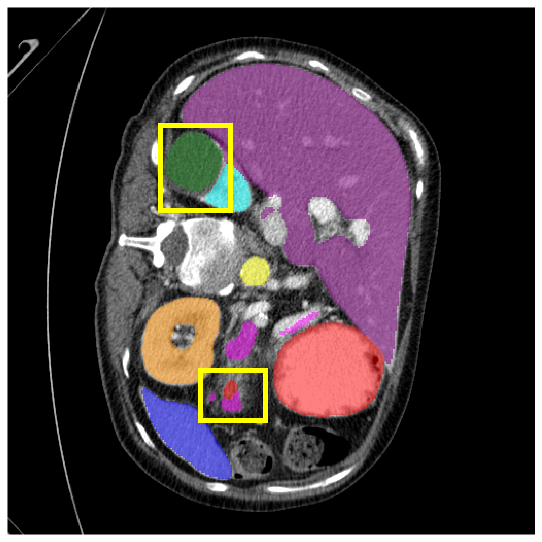

To demonstrate the superiority of our method, additional qualitative comparison results for the ACDC and Synapse datasets are presented in Fig. 6, Fig. 7, respectively. Notably, in the case of GB, the quantitative results in Fig. 7 show relatively lower performance in ‘only ’. However, the visualization results in Fig. 7 reveal instances where the enhanced images identified GB regions that the original images failed to segment, albeit with some boundary over-segmentation. In such scenarios, our proposed method successfully leveraged the information from enhanced images to achieve more accurate GB segmentation. Note that this finding underscores the fact that even when quantitative performance metrics appear lower, the additional information provided by enhanced images can be valuable in the actual segmentation process.

4.3.2 Visual Comparisons

Visualization of our method on the Synapse and ACDC datasets is shown in Fig. 3(a) and Fig. 3(b). For the Synapse dataset illustrated in Fig. 3(a), FCT failed to accurately segment SM and GB, while MERIT achieved precise segmentation of SM but struggled with GB. In contrast, our method achieved accurate segmentation of both SM and GB. Regarding the ACDC dataset shown in Fig. 3(b), while previous methods achieve comparable segmentation of the Myo and LV to the GT, they exhibit noticeable errors on the RV, including invasion into adjacent organs and misrecognition. On the other hand, our method accurately segments across all three structures Myo, LV, and RV, performing as precisely as the GT. We demonstrate the superiority of our method quantitatively and qualitatively.